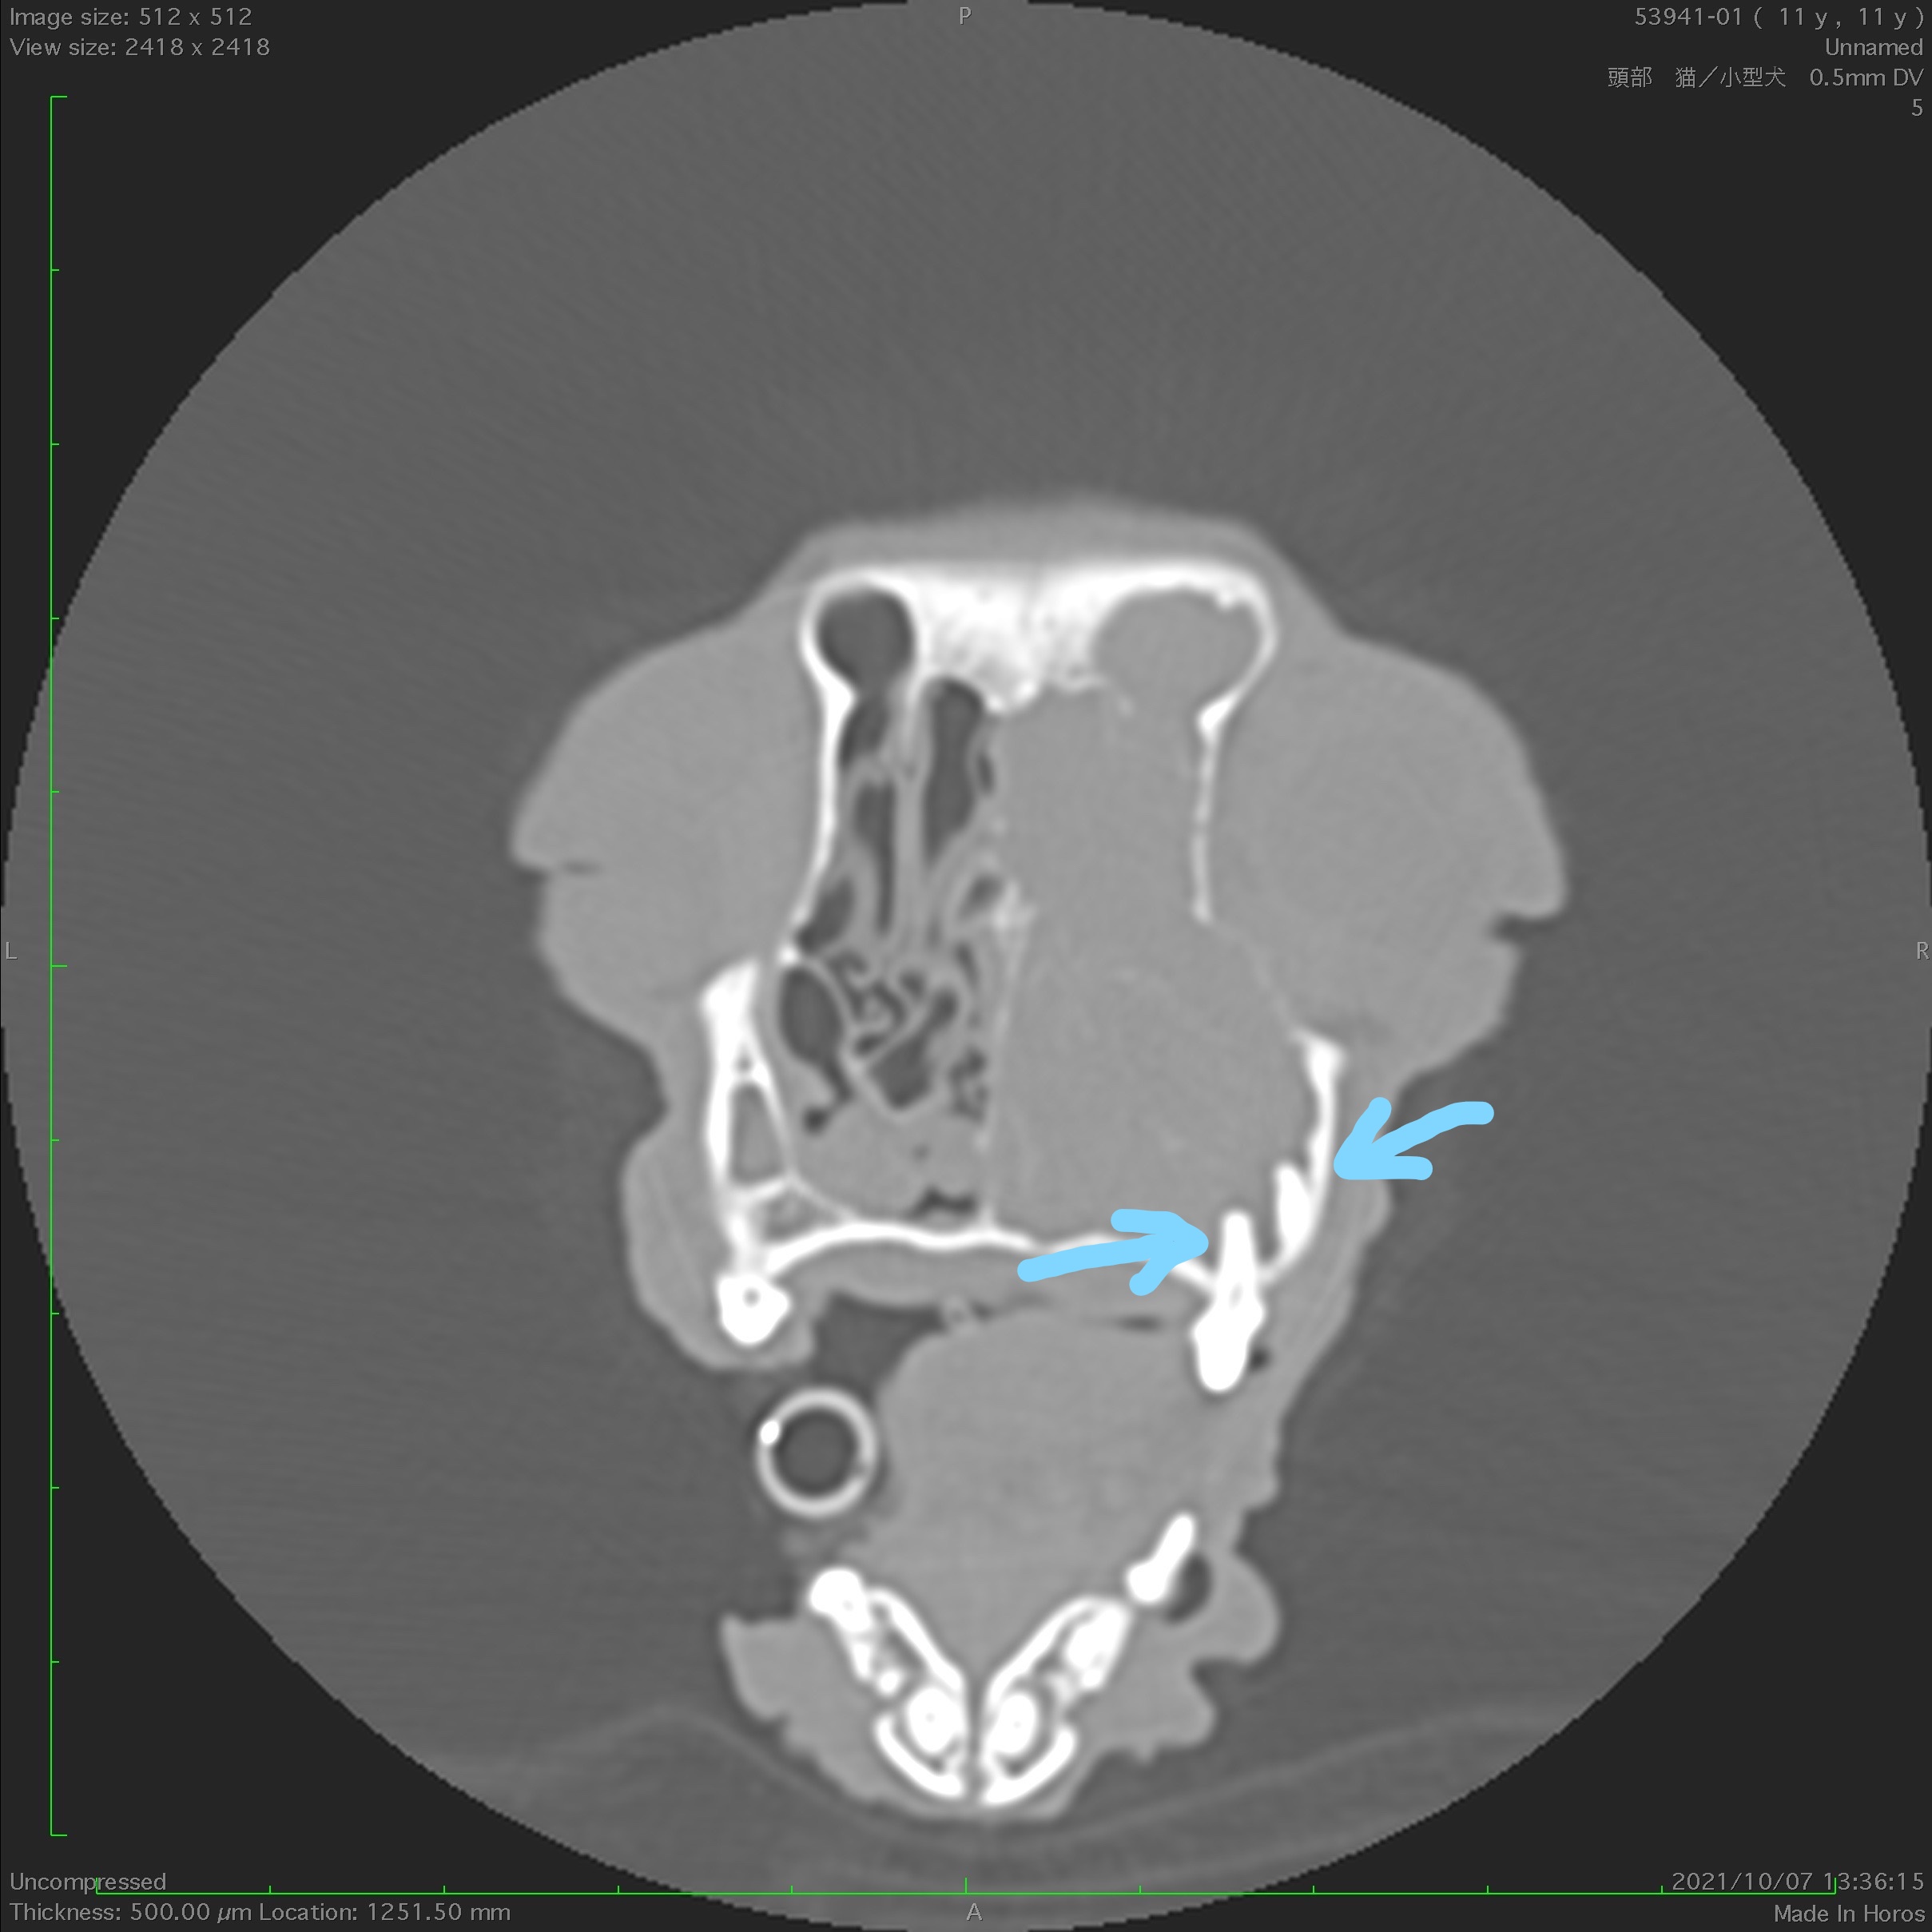

また、鼻の中に腫瘍や異物などの原因があるかどうかを鑑別して調べるためCT検査を実施したとことろ、多量の分泌物がたまっていることが判明しました。

(CT像)矢印部分の歯根と鼻腔が連続しており、片側全体が膿瘍で満たされている